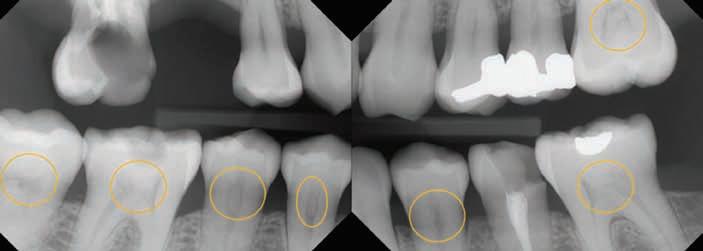

Her full mouth intraoral radiographs revealed generalized pulpal calcifications of various dimensions in the pulp chambers and root canals. In at least one tooth, multiple discrete pulpal calcifications were observed. All teeth with existing pulpal calcifications were asymptomatic, and did not show any radiographic signs of periapical bone loss or periodontal ligament (PDL) widening.

Figure 1. Full mouth radiographic survey reveals multiple pulpal calcifications of various dimensions affecting the pulp chamber and radicular pulp of patient’s remaining dentition.

Figure 2. Full mouth radiographic survey reveals multiple pulpal calcifications of various dimensions affecting the pulp chamber and radicular pulp of patient’s remaining dentition. Multiple discrete pulpal calcifications can be noted on upper left first molar pulp chamber.